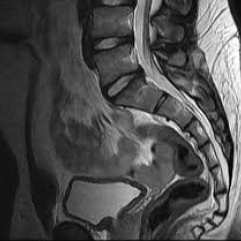

Resonancia nuclear magnetica de columna sacroiliaca simple y contrastada. EN. Codigo 883232 SC (2022)